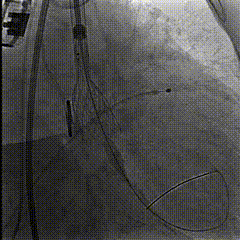

TaurusElite®AV23瓣膜,瓣环下0-2mm偏高位,在左右重合体位下释放。

瓣膜释放至工作体位,一次成功

瓣膜形态位置良好,冠脉灌注良好